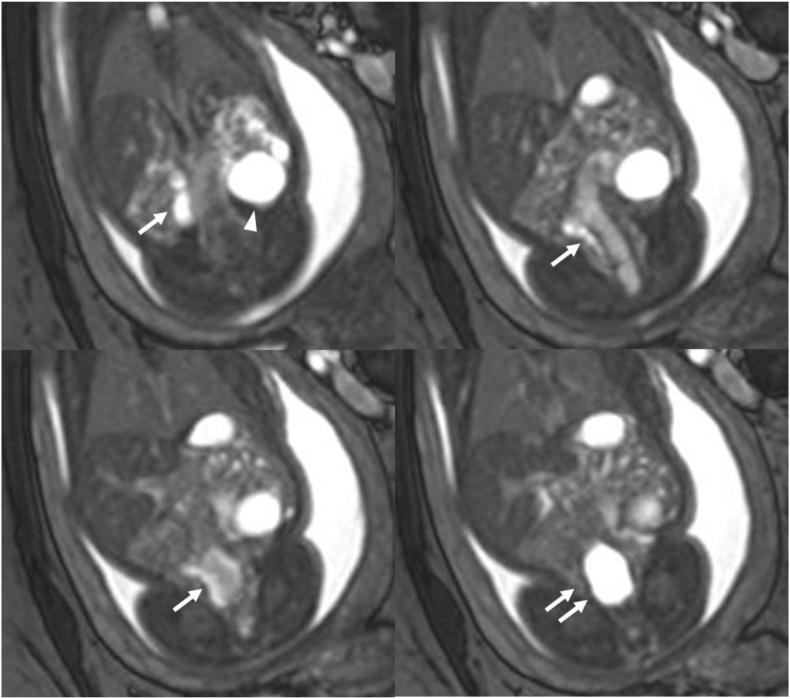

Spontaneous intraperitoneal renal rupture with urinoma formation in the fetus.

Spontaneous intraperitoneal renal rupture with urinoma formation in fetuses is an unusual condition that is caused by upper or lower urinary tract obstruction. We report the case of a neonatal male infant who presented with a spontaneous intraperitoneal right renal rupture accompanying ipsilateral ureterovesical junction obstruction (UVJO). Fetuses with UVJO accompanying contralateral multicystic dysplastic kidney should be observed carefully because of the risk of spontaneous renal rupture.